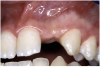

Periapical radiographs were taken to help determine the mesial-distal inclinations of the adjacent tooth roots (Figure 1). The radiographs revealed a serious issue, convergent roots for the right canine and right central, which eliminated that area as a potential implant-receptor site. The space between the left central and canine teeth was minimal, although the roots were relatively parallel. Clinical examination (manual palpation of the root eminences superiorly to the vestibule on the right side) confirmed the root convergence (Figure 2A). The flat, wide zone of the keratinized tissue and lack of interdental papilla was evident for the missing right lateral incisor. There was a marked difference in clinical appearance for the left lateral, which could impact the eventual plan of treatment (Figure 2B). Other significant clinical findings included bilateral facial bone concavities, which existed as a result of the congenitally missing tooth roots. As a diagnostic cue to the underlying bone topography, it is important to follow the demarcation between attached and unattached gingival tissue, and note the crestal width of the available keratinized tissue (Figure 2C).

Figure 2b  Pretreatment buccal views showed (A) root convergence, (B) a difference in clinical appearance of the left lateral, and (C) significant crestal width of keratinized tissue.

Figure 2b

Figure 2c  Pretreatment buccal views showed (A) root convergence, (B) a difference in clinical appearance of the left lateral, and (C) significant crestal width of keratinized tissue.

Figure 2c